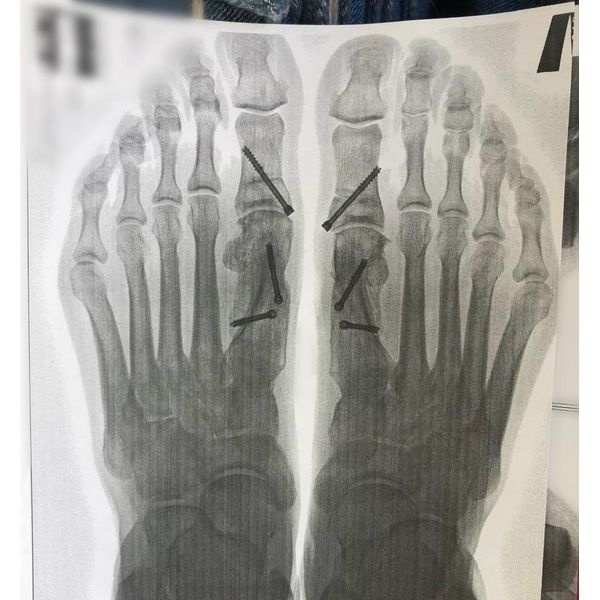

- рентгенографии стоп (в прямой и боковой проекции): выявлено вальгусное отклонение первых пальцев (угол > 40°), медиальное отклонение первых плюсневых костей;

- остеотомия (рассечение кости для исправления деформации) SCARF с фиксацией винтами, коррекция плюснефалангового угла;

Рентгенограмма подтвердила правильное положение первых пальцев стоп. Профилактические меры (ЛФК и ношение ортопедических стелек) помогли сохранить достигнутый результат.